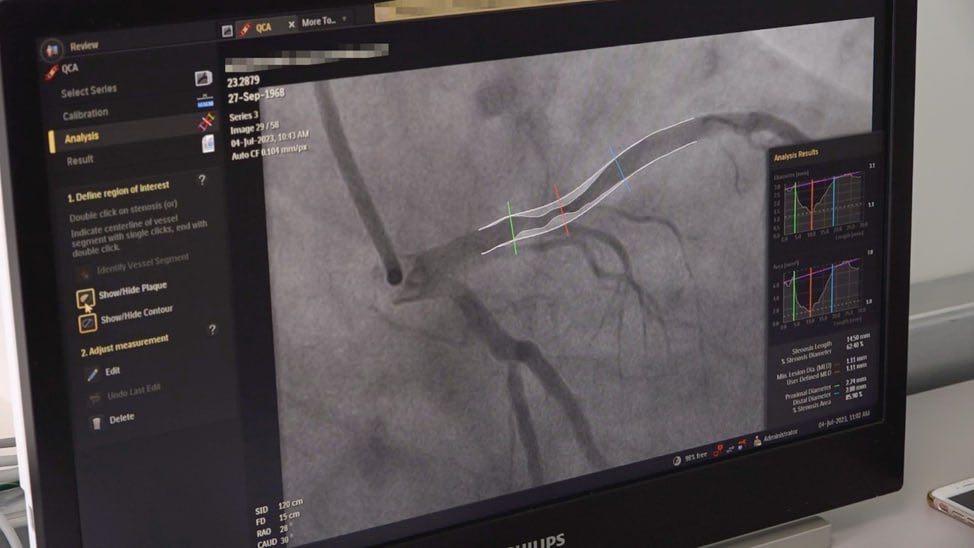

По данным Территориального органа Росздравнадзора по Воронежской области, в ФГБУЗ «КБ № 33 ФМБА России» (город Нововоронеж) начало функционировать отделение рентгенохирургических методов диагностики и лечения (РХМДиЛ).

В день открытия отделения в рентген-операционной были успешно проведены операции коронароангиографии первым пациентам.

Отделение полностью оснащено новейшим современным оборудованием для проведения диагностических исследований и вмешательств на сосудистой системе. Жители города  Нововоронежа, Каширского и Репьевского районов Воронежской области будут здесь получать высокотехнологичную медицинскую помощь, в основе которой лежат малоинвазивные методы лечения, направленные на устранение патологии аорты, коронарных и периферических сосудов, коррекцию врожденных и приобретенных пороков сердца, а также профилактику тромбоэмболических осложнений.

Имеющийся в отделении ангиографический комплекс соответствует стандартам рентгенологической безопасности, как для врача, так и для пациента, в связи с использованием ультранизких доз излучения и повышенной разрешающей способности.